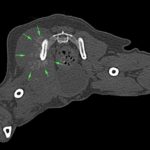

鎮痛剤で跛行が改善しないワンコの精査依頼がありました。CTでは股関節(主に腸骨)に骨融解像が確認されました。細胞診では悪性腫瘍と暫定診断が行われました。除痛のため半側骨盤切除で対応しました。後肢を失うことは大変辛いことですが、ワンコは痛みがなくなり快適に過ごせているそうです。一見、整形外科に見えても高齢犬には腫瘍が隠れていることがあるのでCTによる精査は大変有効です。